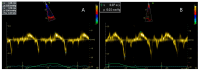

Duchenne Muscular Dystrophy (DMD) is a severe X-linked recessive disorder characterized by progressive muscle degeneration due to dystrophin deficiency. Cardiac involvement, particularly dilated cardiomyopathy, significantly impacts morbidity and mortality, typically manifesting after age 10. This case report presents a rare instance of early-onset cardiac involvement in a 3-year-old male with a confirmed deletion in exon 55 of the dystrophin gene. The patient developed dilated cardiomyopathy at 3 years and 8 months, with progressive left ventricular dysfunction despite early treatment with corticosteroids, ACE inhibitors, and beta-blockers. Genetic mechanisms and genotype-phenotype correlations related to cardiac involvement were reviewed, highlighting emerging therapies such as exon skipping, vamorolone, ifetroban, and rimeporide. Studies indicate that variants in exons 12, 14-17, 31-42, 45, and 48-49 are associated with more severe cardiac impairment. This case emphasizes the need for early, ongoing cardiac assessment and personalized treatment to address disease heterogeneity. While current DMD care standards improve survival, optimizing management through early intervention and novel therapies remains essential. Further research is needed to better understand genotype-phenotype correlations and improve cardiac outcomes for patients with DMD.